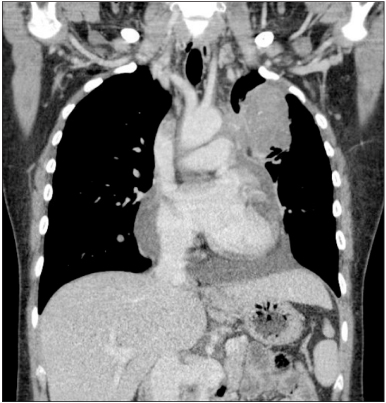

Fig. 2

Chest computed tomography. It reveals a 10×6 cm sized huge mass in left upper lung and massive right sided pleural effusion.

Fig. 2 Chest computed tomography. It reveals a 10×6 cm sized huge mass in left upper lung and massive right sided pleural effusion.